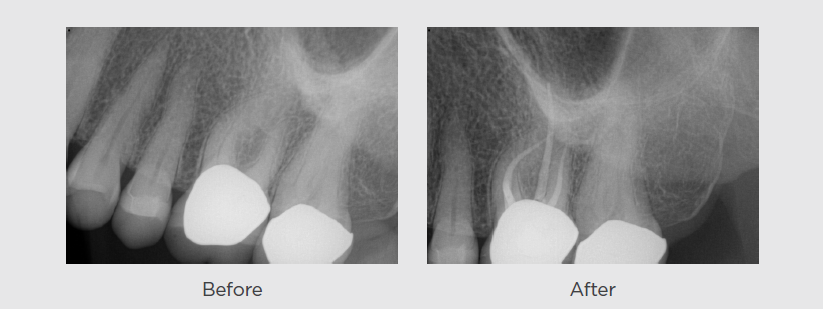

The patient presented with temperature sensitivity in the upper left quadrant

The Case: The patient presented with temperature sensitivity in the upper left quadrant. The exam confirmed that tooth #14 was…